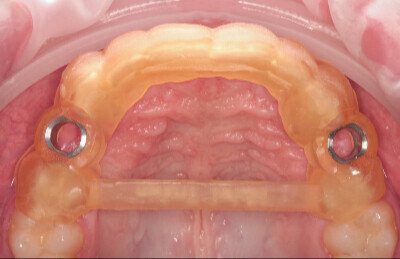

Navigovaná chirurgia, 3 implantátov

Autor práce Dr. Michal Repaši

Zubný technik Vasil Csopej